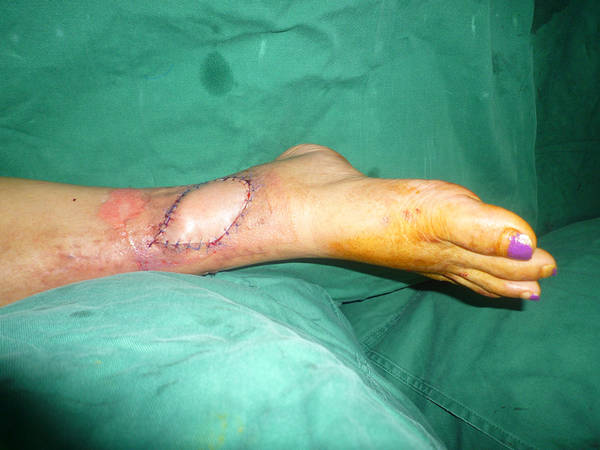

[组织瓣] 改良外踝上皮瓣的再次改良

看看吧这个皮瓣有什么不一样的地方?

以腓动脉穿支为蒂,皮瓣只靠穿支供血,改良的地方是将皮瓣 通过皮下隧道部的分皮肤保留在原位。这样蒂部宽松,平整,又不浪费皮肤,减少手术创伤。

改良中的改良

蒂部不带皮肤,皮下隧道

1蒂部不带皮肤了2皮下隧道=外观更美。